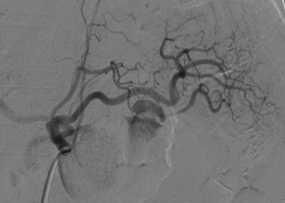

A 60-years-old white male patient sought the emergency room of the Hospital de Base de São José do Rio Preto-Brazil, complaining of the appearance of an ulcerated wound in the distal third of the left lower limb for 20 days. Alcoholic, smoker and previous diagnosis of chronic pancreatitis. On physical examination, upon admission, the abdomen was normotensive, painless on palpation and without masses or visceromegaly. During the investigation of this ulcer and 12 hours after admission, the patient developed diffuse abdominal pain and distension, more intense in the upper abdomen and associated with peritonitis. Computed tomography of the upper abdomen and pelvis was performed, which showed a pseudoaneurysm of the dorsal artery of the pancreas with frank extravasation of contrast into the abdominal cavity, in addition to a moderate amount of free blood around the liver (Figure 1).

Figure 1 Initial abdominal and pelvis tomography which showed a pseudo aneurysm of the dorsal artery.